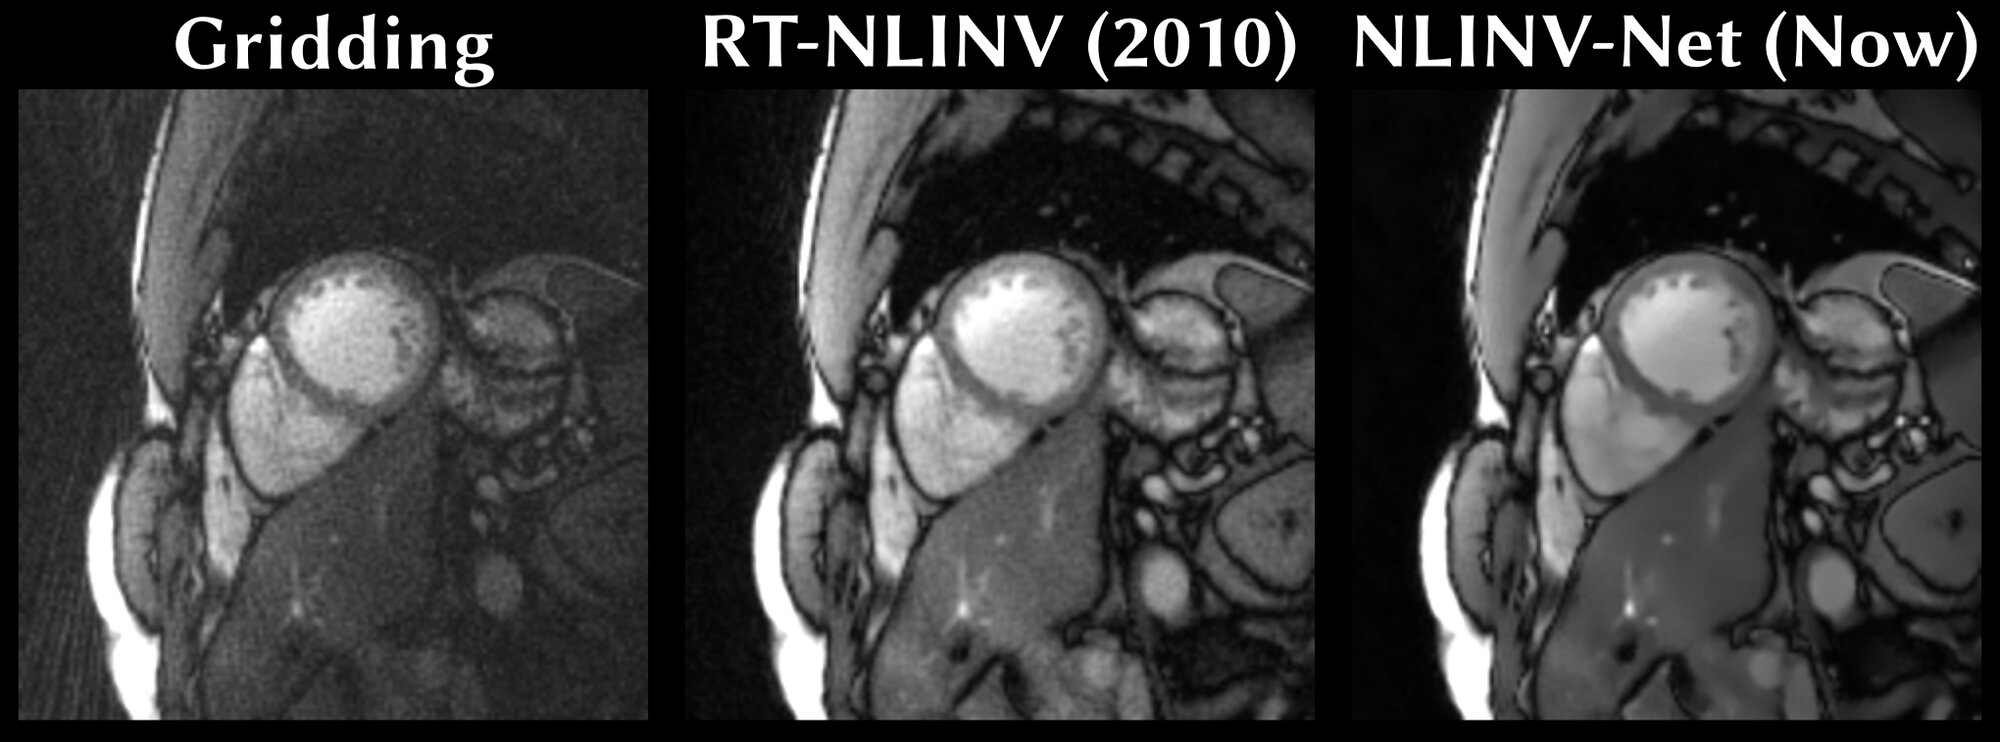

Die medizinische Bildgebung mittels Magnetresonanztomografie (MRT) ist sehr zeitaufwändig, da ein Bild aus Daten von vielen Einzelmessungen zusammengesetzt werden muss. Durch den Einsatz von Machine Learning kann die Bildgebung auch mit weniger MRT-Messdaten gelingen. Dies kann Zeit und Kosten sparen. Die Voraussetzung dafür aber sind perfekte Bilder, um damit die KI-Modelle zu trainieren. Für gewisse Anwendungen wie z.B. Echtzeit-Bewegtbild-MRT gibt es solche perfekten Trainingsbilder nicht, da solche Aufnahmen bisher immer etwas unscharf sind. Einem internationalen Forschungsteam um Martin Uecker und Moritz Blumenthal vom Institute of Biomedical Imaging an der TU Graz ist es nun mithilfe speziell trainierter neuronaler Netze gelungen, präzise Live-MRT-Bilder des schlagenden Herzens auch ohne solche Trainingsbilder und mit nur sehr wenigen MRT-Daten zu erzeugen. Durch diese Verbesserungen könnte die Echtzeit-Bewegtbild-MRT zukünftig häufiger in der Praxis zum Einsatz kommen.

Um ihr Machine-Learning-Modell für die MRT-Bildgebung zu trainieren, nutzten Uecker und Blumenthal Methoden des „Self-supervised Learnings“: Dabei sind nicht vorab kuratierte perfekte Bilder die Grundlage zum Trainieren des Modells, sondern eine Teilmenge der Ausgangsdaten, aus denen das Modell die Bilder rekonstruieren soll. Blumenthal erklärt es so: „Wir haben die vom MRT-Gerät gelieferten Messdaten in zwei Portionen aufgeteilt. Aus der ersten, größeren Datenportion rekonstruiert unser Machine-Learning-Modell das Bild. Anschließend versucht es, auf Basis des Bildes die ihm vorenthaltene, zweite Portion der Messdaten zu berechnen.“ Gelinge dem System dies nicht oder nur schlecht – so die zugrundeliegende Logik –, müsse das zuvor rekonstruierte Bild falsch gewesen sein. Das Modell werde aktualisiert, es erstelle eine neue verbesserte Bildvariante und versuche erneut, die zweite Datenportion zu berechnen. Dieser Vorgang laufe über eine Vielzahl von Runden, bis das Ergebnis stimmig sei. Dabei lerne das System aus einer Vielzahl solcher Rekonstruktionen in diesem Trainingsprozess, wie gute MRT-Bilder aussehen sollten. Später, während der Anwendung, könne das Modell dann direkt ein gutes Bild berechnen.